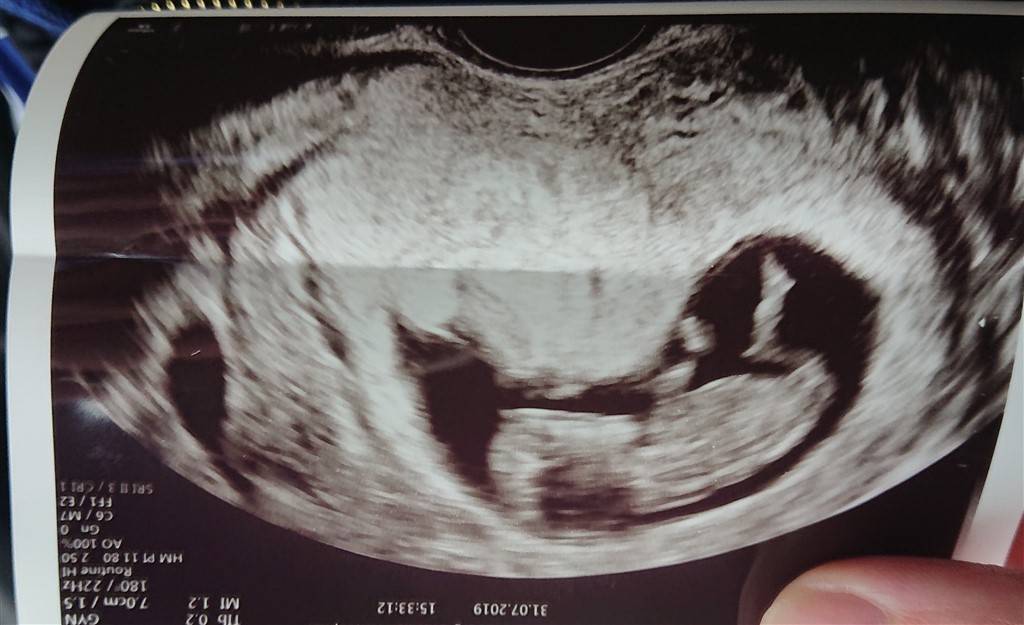

Jeg ved godt i ikke kan sige det med sikkerhed, men nogle der kan "se" kønnet ud fra teorien? Jeg kan ikke selv gennemskue det

Helt klart pige, rigtig flot billede

Pige.

11+0

Så er det desværre alt for tidligt at bruge nub teorien. Da kønsdelene ikke er færdig udviklet